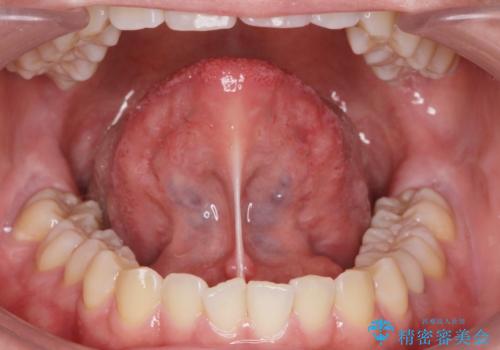

- 40代男性

- 寝ている間に歯ぎしりをしている気がするとの事で来院。

過去にナイトガードを使用したことがあったが穴が空いてしまったそうです。

ナイトガードを使用することによって歯がすり減る(寝ている時の歯ぎしりなど)事を防いでくれます。